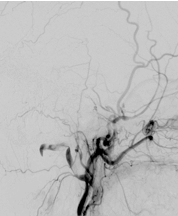

Ist eine AV-Fistel durch MRT und eine diagnostische Angiographie sicher nachgewiesen, gibt es in Abhängigkeit von der Lage und Ausdehnung der Fistel verschiedene endovaskuläre Behandlungsoptionen. Heute wird in den meisten Fällen versucht, die AV-Fistel unter Erhalt der venösen Blutleiter zu veröden (Embolisation). Hierfür wird ein sehr dünner Katheter („Mikrokatheter“) über die Leiste bis in die Fistelgefäße geführt. Dies geschieht unter Vollnarkose. Über den Katheter wird ein Embolisat in die Fistelgefäße gespritzt, um diese zu verkleben bzw. zu verstopfen. Für die Embolisation kommen verschiedene Materialien zur Anwendung, überlicherweise werden heute Flüssigembolisate verwendet. Bei ausgedehnten Fisteln kann ein Ballonkatheter über die Leistenvene in den beteiligten venösen Blutleiter in das Gehirn eingelegt werden, um die Vene während der Embolisation vor einer Verstopfung durch das Flüssigembolisat zu schützen. Je nach Größe und Lokalisation der Fistel sind mitunter mehrere Behandlungen notwendig.